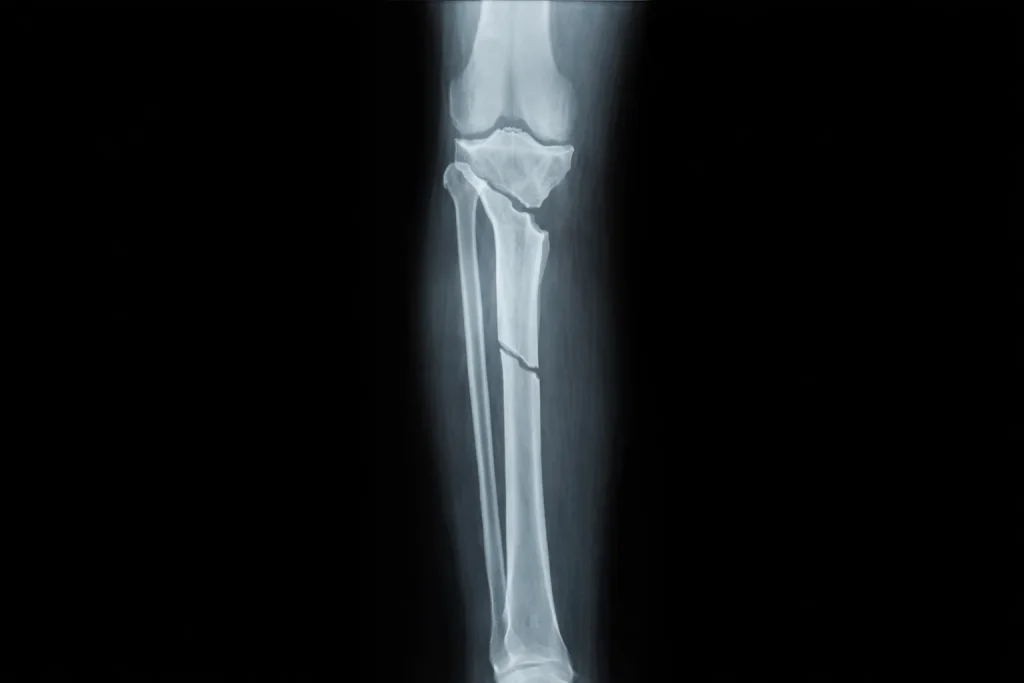

X-rays are the primary diagnostic tool for confirming a femur fracture. Technicians will take images from multiple angles-typically front-to-back and side views-to fully visualize the break.

X-rays clearly show:

- The exact location of the fracture along the shaft

- The fracture pattern (transverse, oblique, spiral, or comminuted)

- How displaced the bone fragments are

- Whether the break extends into nearby joints